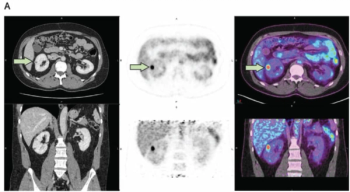

Results from a multicenter phase 3 trial showed that the PET/CT imaging agent (89Zr)Zr-girentuximab had an 85.5 percent mean sensitivity rate for the diagnosis of clear cell renal cell carcinoma.